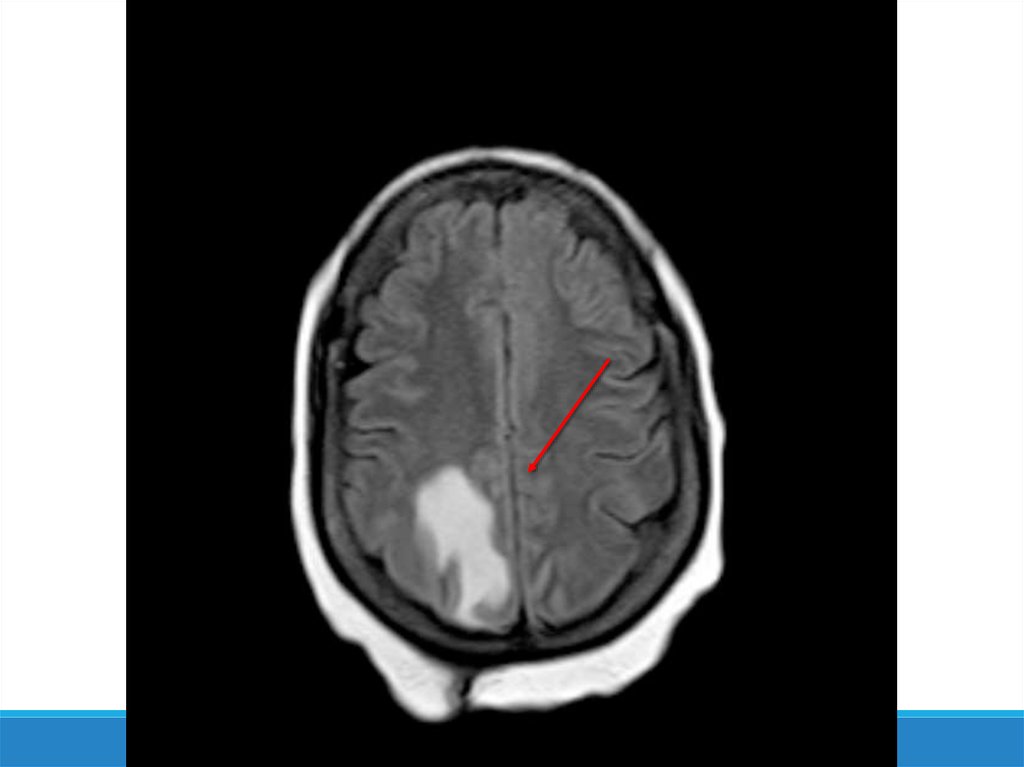

-Компьютерная томография

-Магнитно-резонансная

томография